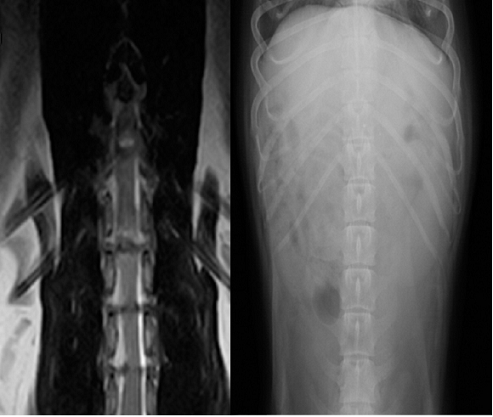

【画像診断】~ダックスフンド、雄10歳、グレート3の椎間板ヘルニア~

▲椎間板ヘルニアがあるMRI像、冠状断像T13-L1の造影なしのT2強調画像、T2強調の矢状断面(キャミックに依頼)

▲ダックスフンド、病変部は胸椎T13-腰椎L1の単純X線検査像の側面像